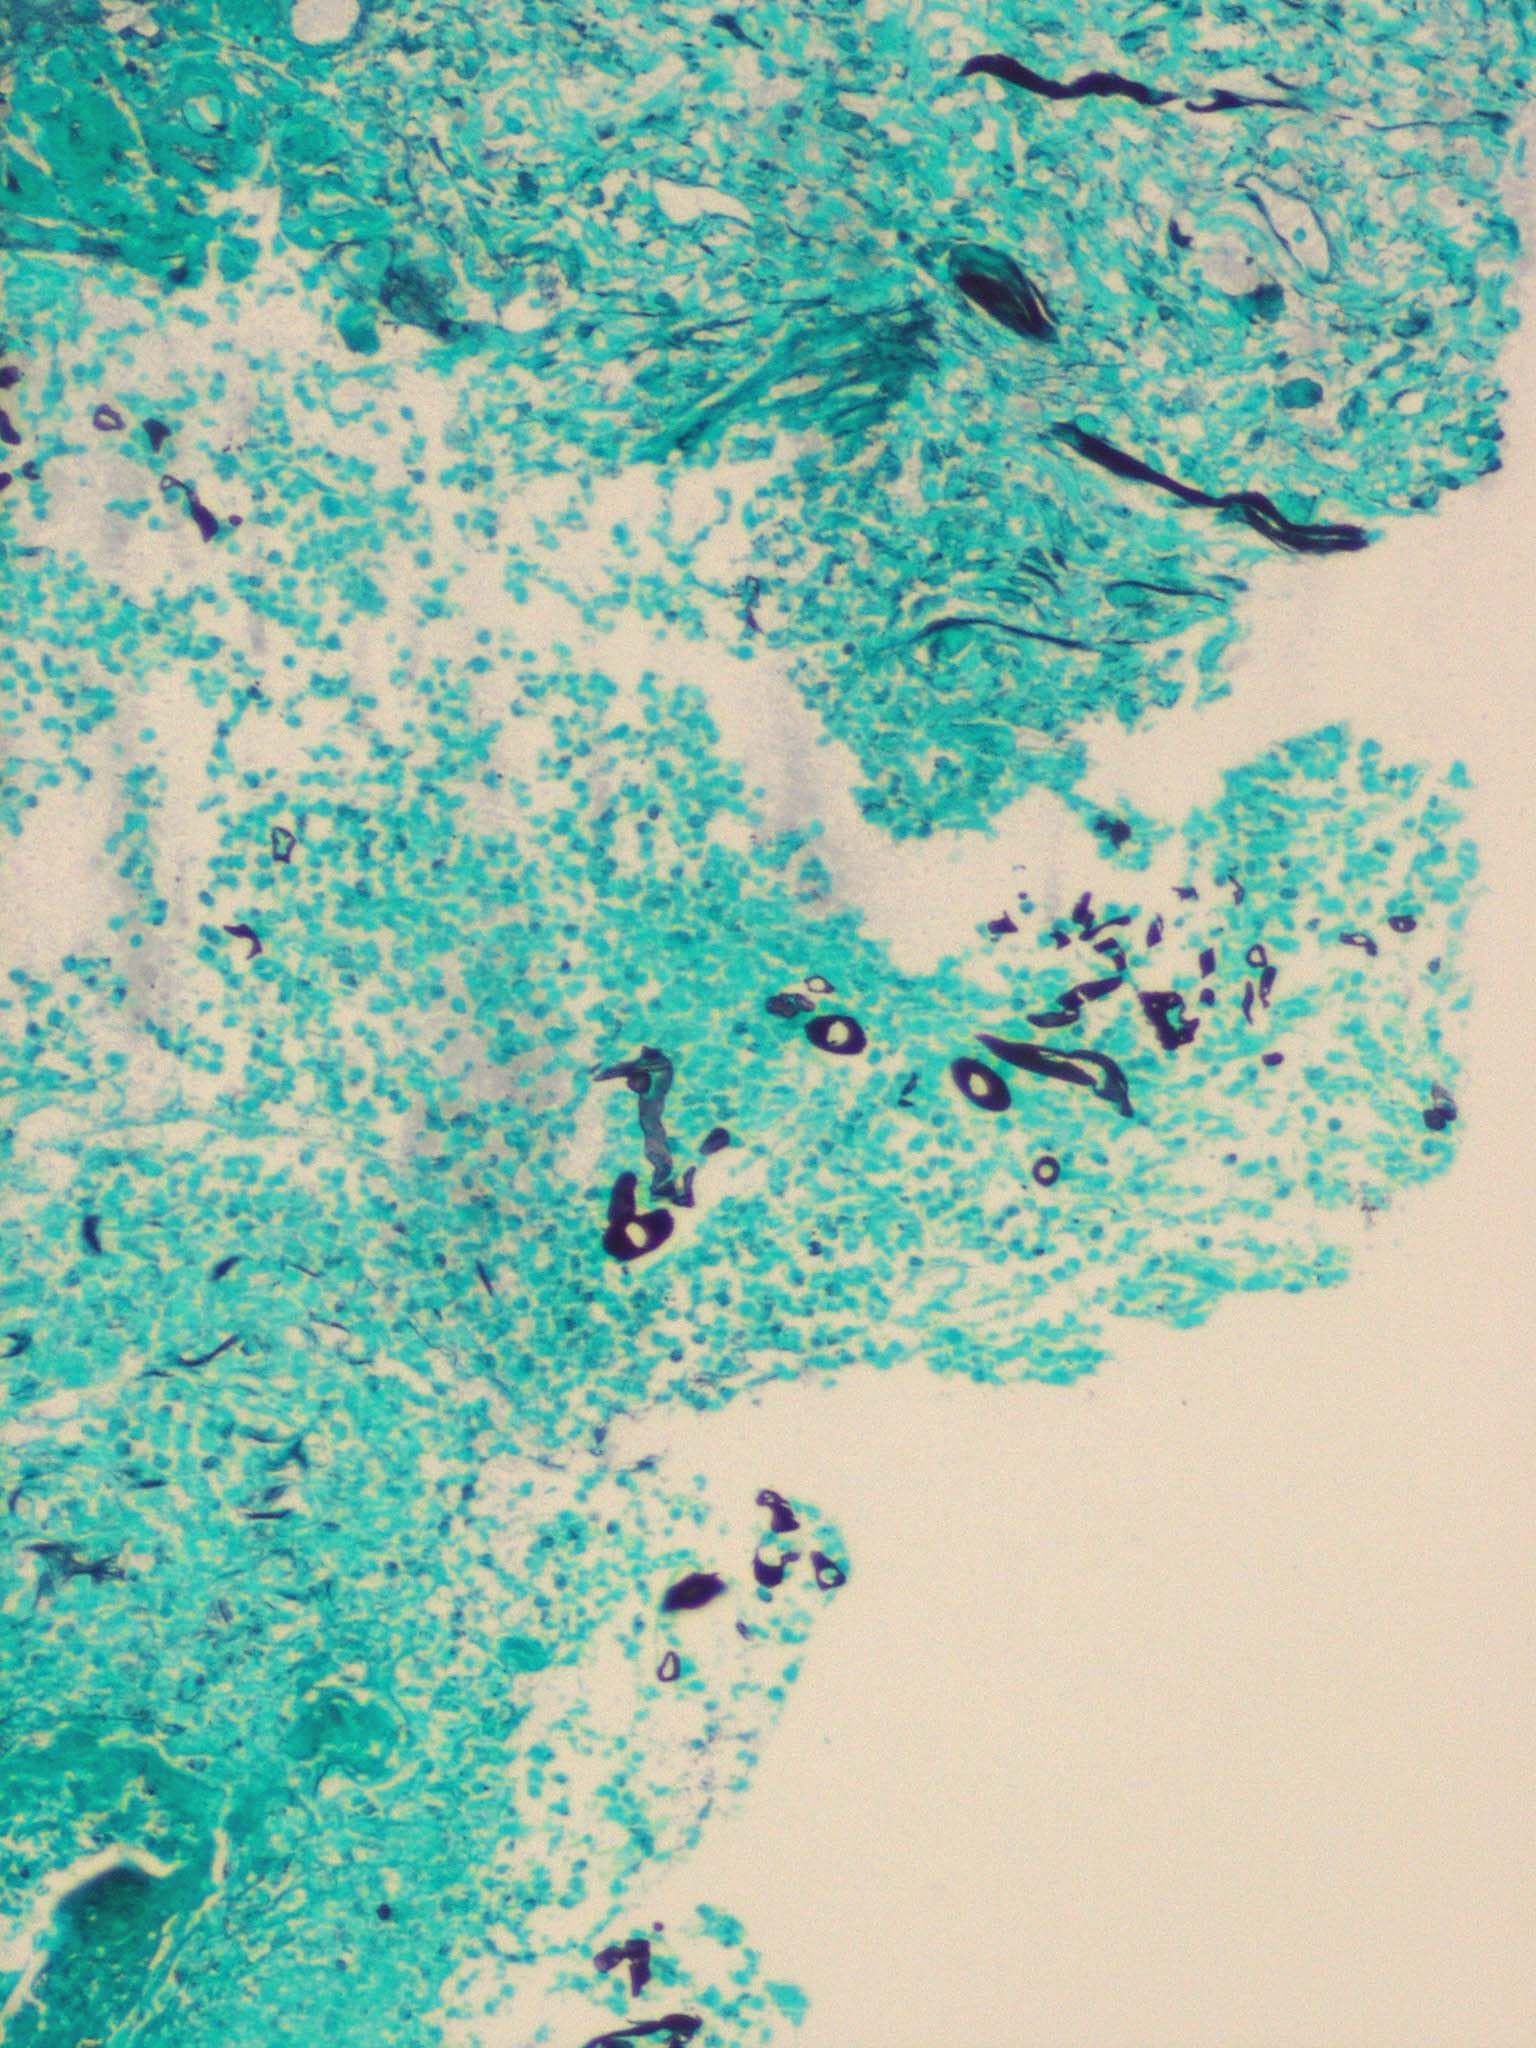

Zygomycosis =فطار عفني